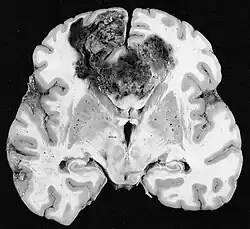

Glioblastome

Les tumeurs des cellules gliales les plus courantes et les plus malignes sont les glioblastomes. Ils consistent en une masse hétérogène de cellules d'astrocytome peu différenciées principalement chez l'adulte. Ils surviennent généralement dans les hémisphères cérébraux, plus rarement dans le tronc cérébral ou la moelle épinière. Sauf dans de très rares cas, comme toutes les tumeurs cérébrales, elles ne s'étendent pas au-delà des structures du système nerveux central.

Le glioblastome peut provenir d'une forme diffuse (II. grade) ou un astrocytome anaplasique (III. grade) développer. Dans ce dernier cas, il est dit secondaire. Cependant, lorsqu'elle survient sans antécédent ni signe de malignité antérieure, on parle de maladie primaire. Les glioblastomes sont traités par chirurgie, radiothérapie et chimiothérapie. Ils sont difficiles à guérir et rares sont les cas qui survivent au-delà de trois ans.

Sur-L'IRM montre une tumeur intracrânienne comme une lésion massive qui peut devenir plus luminescente après utilisation du produit de contraste. Cependant, il y a toujours une anomalie de signal dans -L'imagerie par résonance magnétique, qui indique la présence d'une néoplasie ou d'un œdème vasogénique. Habituellement, une luminescence accrue (amélioration du contraste) indique une tumeur d'un grade supérieur de malignité. Un anneau de contraste est caractéristique du glioblastome, avec la partie luminescente correspondant à la partie vitale de la tumeur maligne, et la plus foncée - zone hypointense correspondant à une nécrose tissulaire.